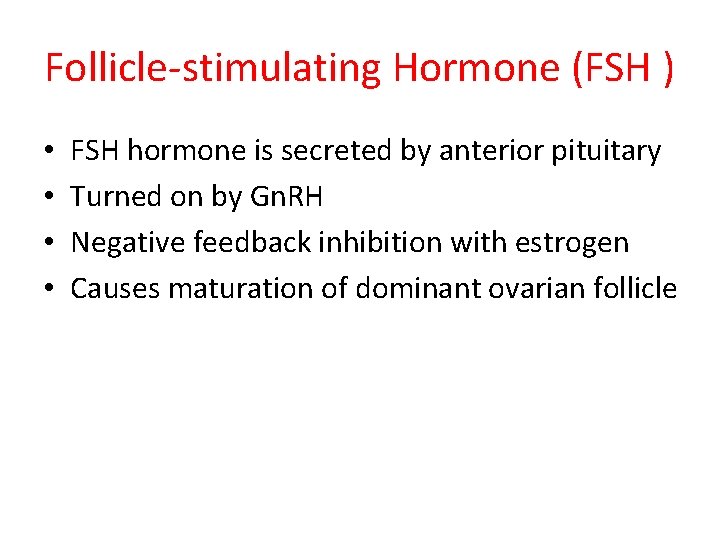

Follicle-stimulating Hormone (FSH ) • • FSH hormone is secreted by anterior pituitary Turned on by Gn. RH Negative feedback inhibition with estrogen Causes maturation of dominant ovarian follicle